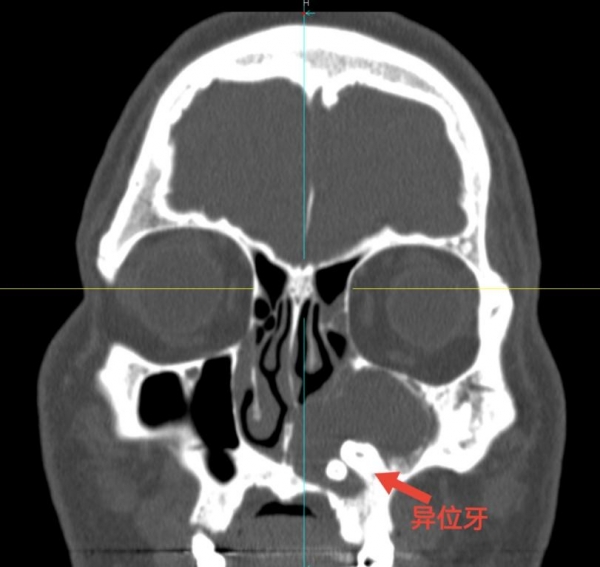

40岁的张先生在1个月前左侧面部开始出现肿胀压痛,自服了抗炎药也没有明显好转,因此他便来到泰康同济(武汉)医院皮肤科就诊。皮肤科医生为张先生安排了头部CT检查,检查后才发现原来困扰张先生的病根竟在鼻子里,他的鼻窦里竟然长了两颗类似牙齿的物质。

耳鼻咽喉科王美荣主任在详细询问病史及现场看诊后,结合CT检查结果,判断是张先生的左侧鼻窦长了两颗异位牙,由此引发的牙源性囊肿破坏了周围结构,进而引起了面部红肿压痛。